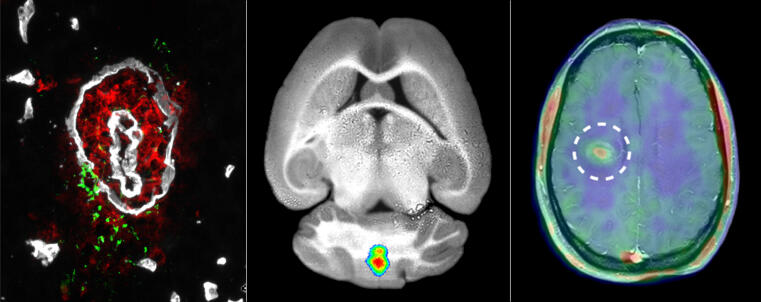

Left picture: Blood vessels of the brain (white, cross-section) have a special structure that makes them particularly tight (impermeable), establishing the so-called blood-brain barrier. CiM researchers have found that specific enzymes, matrix metalloproteinases (MMPs, green), are crucial for immune cell (red) penetration of this barrier (white) to cause inflammation in the brain. Centre picture: Using a fluorescent MMP tracer, initially in mice, researchers were able to visualize active MMPs only at site of inflammation in the brain. Right picture: A radioactively labelled variant of the tracer accumulated in a defined area (right) in the brain of a MS patient with an acute attack of multiple sclerosis, but not after anti-inflammatory therapy.

Blood vessel in a mouse's brain (cross-section, fluorescence microscopy). Immune cells (leukocytes, shown in red) penetrate the blood-brain barrier and migrate to the brain (from centre to edge of the images). Left picture: The immune cells overcome a first barrier (inner circular structure, shown in white) which is a layer of endothelial cells and their underlying basement membrane. Right picture: The second barrier (outer circular structure), which only exists in blood vessels of the brain, is an extra basement membrane and a layer of special neural cells, the astrocytes. CiM researchers have discovered that enzymes, matrix metalloproteinases (MMPs, shown in green) – become activated only upon penetration of the second barrier, promoting immune cell migration into the brain and the appearance of disease symptoms. This would be equivalent to an immunological flare in a MS patient.

Inflammation in a mouse’s brain (fluorescence reflectance imaging).

© Hanna Gerwien, Andreas Faust, Lydia Sorokin, Michael Schäfers

To make the tiny structures in a mouse’s brain visible, the chemists linked the MMP tracer to a fluorescent tag. The fluorescence light signal from such a tracer can be measured using optical imaging techniques. Dr. Hanna Gerwien, who has just completed her PhD in biology, injected the tracer into diseased mice and examined the animals using fluorescence ­reflectance imaging. This technique visualizes the fluorescent tracers in the near-infrared range in a living organism. The researchers discovered that the tracer accumulated in high ­concentrations in certain parts of the brain.

To investigate whether the tracer signal correlated with MMP activity at the blood-brain barrier and with immune cell infiltration, Hanna Gerwien removed the brain and examined it under the microscope. The result was that the localization of MMP activity and immune cells matched the fluorescence tracer signal. “We found that our observations of MMP activity provided precise information on where the immune cells penetrate the blood-brain barrier and where inflammation occurs in the brain,” says Hanna Gerwien.